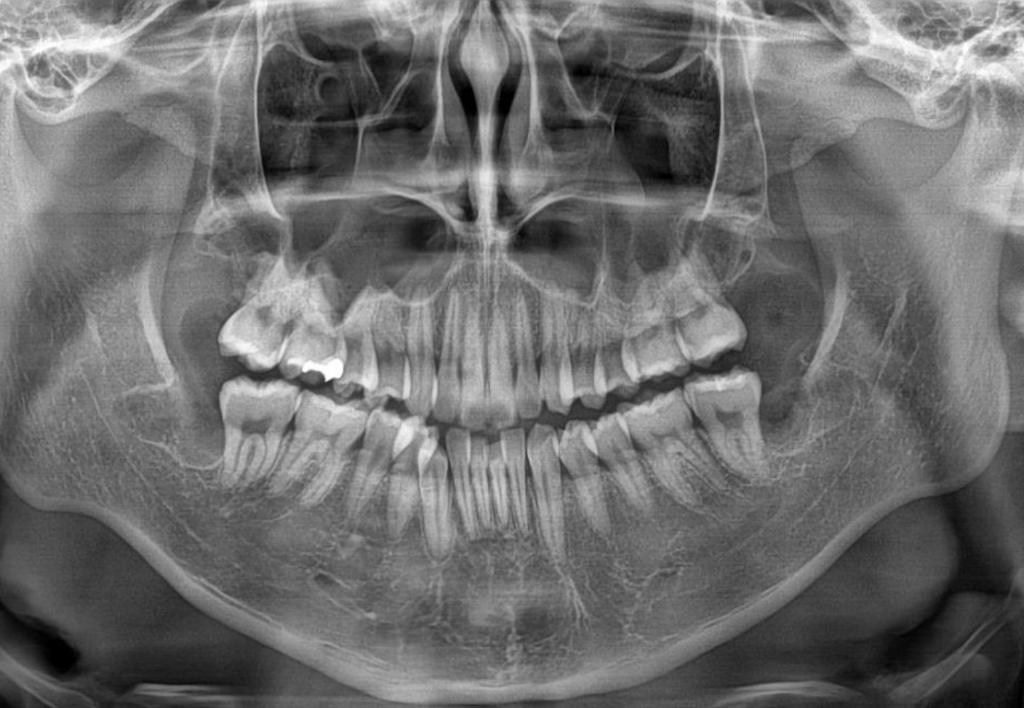

4.발치 후 사진을 봤을때 잘 마무리 되었을까요?

예상되는 부작용(상악천공,신경손상 등)은 없을지

궁금합니다

발치 후

• 2번 째 사진

-별문제 없이 발치를 잘하신거 같습니다.

가격도 괜찮고 치료도 잘 받으신 것 같습니다. 문제가 없어보입니다. 시간이 지나면서 점차 완전 회복되실겁니다.

비용 적당한것 같고..실비는 보험회사에 문의 해야 하고..발치시기 이르지 않고..발치후 문제가 있어 보이지는 않습니다..